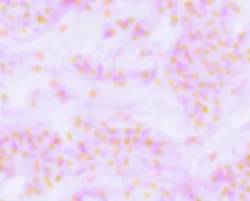

Cellular Structure Up Close

Truvivo Cell Up Close